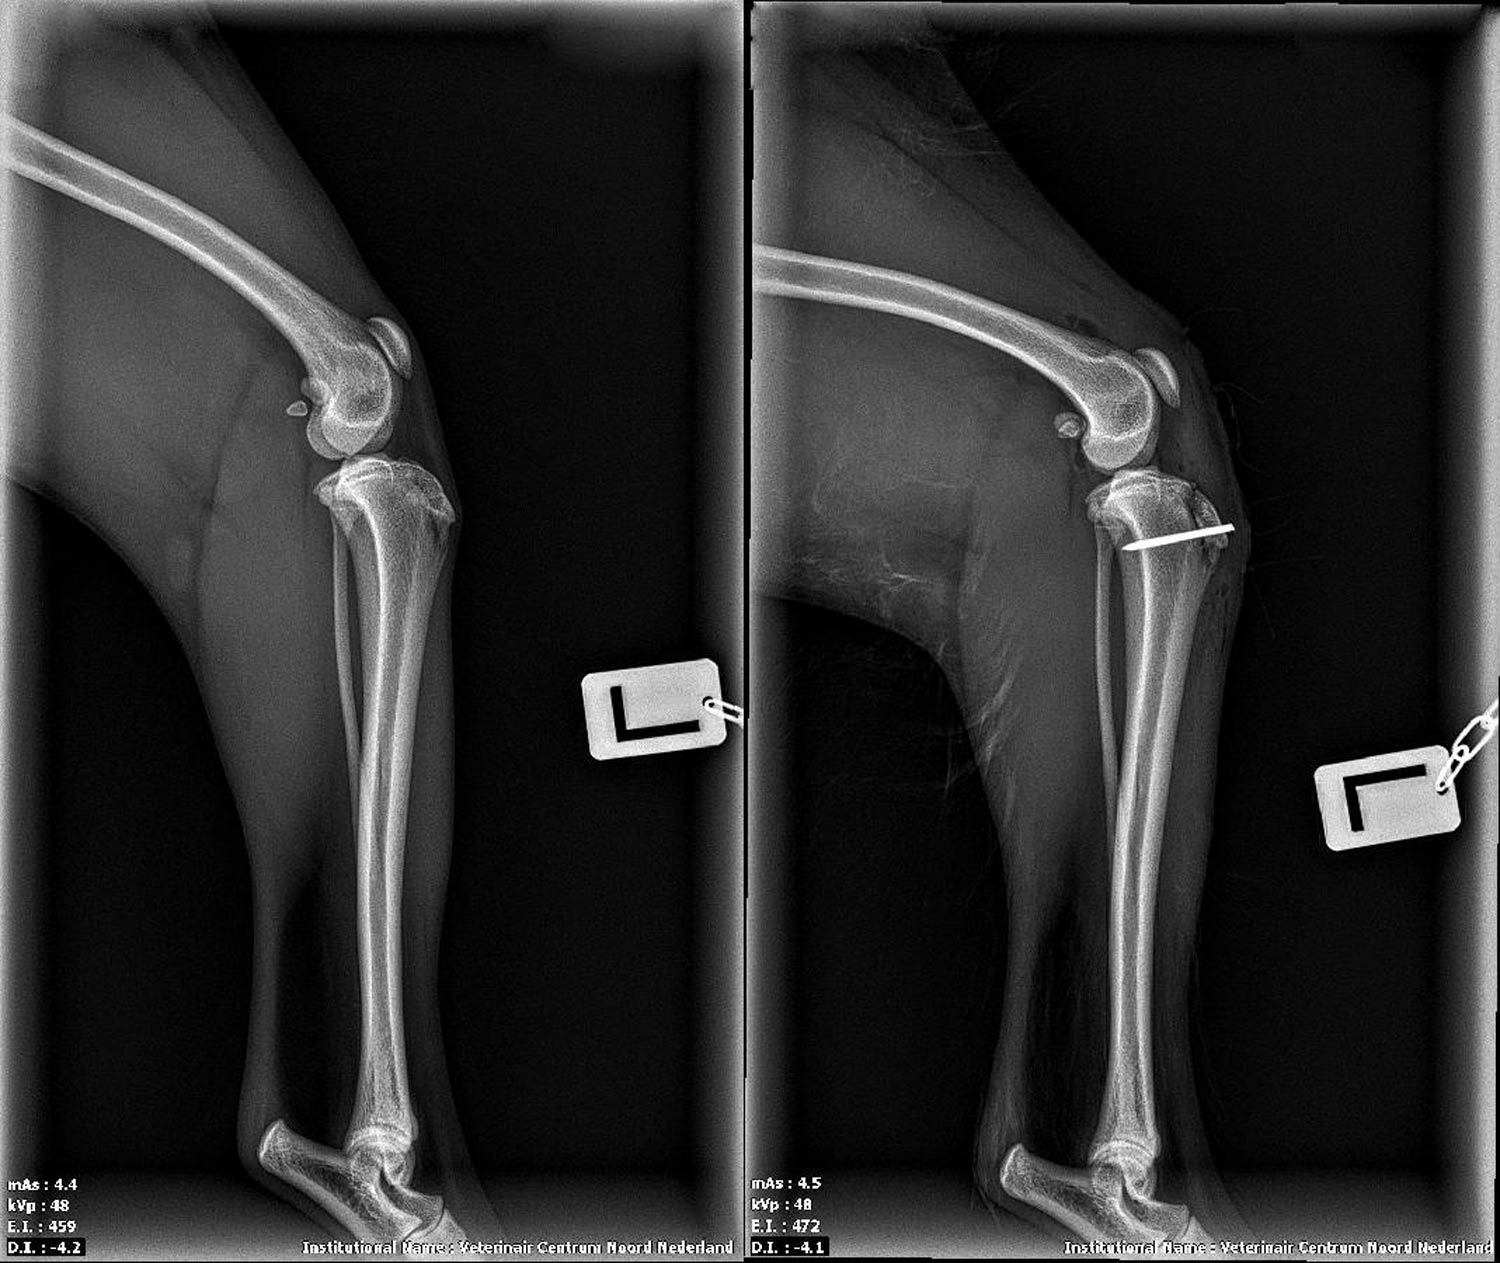

Röntgenfoto vóór en na de operatie